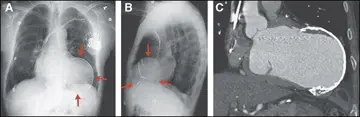

آنوریسم بطن چپ